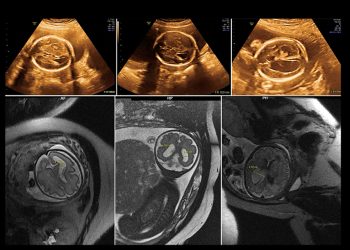

The Amniocentesis Procedure Amniocentesis is typically performed in...